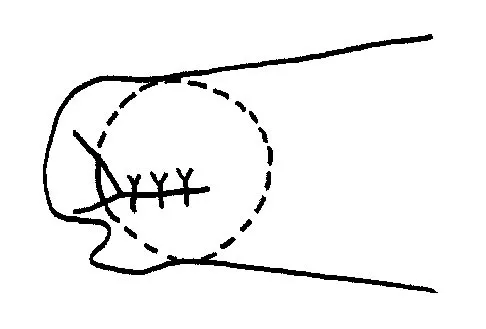

An active 55-year-old man who felt a sudden pop in the left heel while playing tennis 6 months ago was diagnosed with an ankle sprain around the time of injury. He now reports calf atrophy and severe weakness with running. Examination reveals a palpable defect in the Achilles tendon and only trace passive ankle flexion when the calf is squeezed. At the time of surgery, an Achilles tendon defect of 6 cm cannot be approximated. Surgical management of the Achilles tendon should include

Explanation